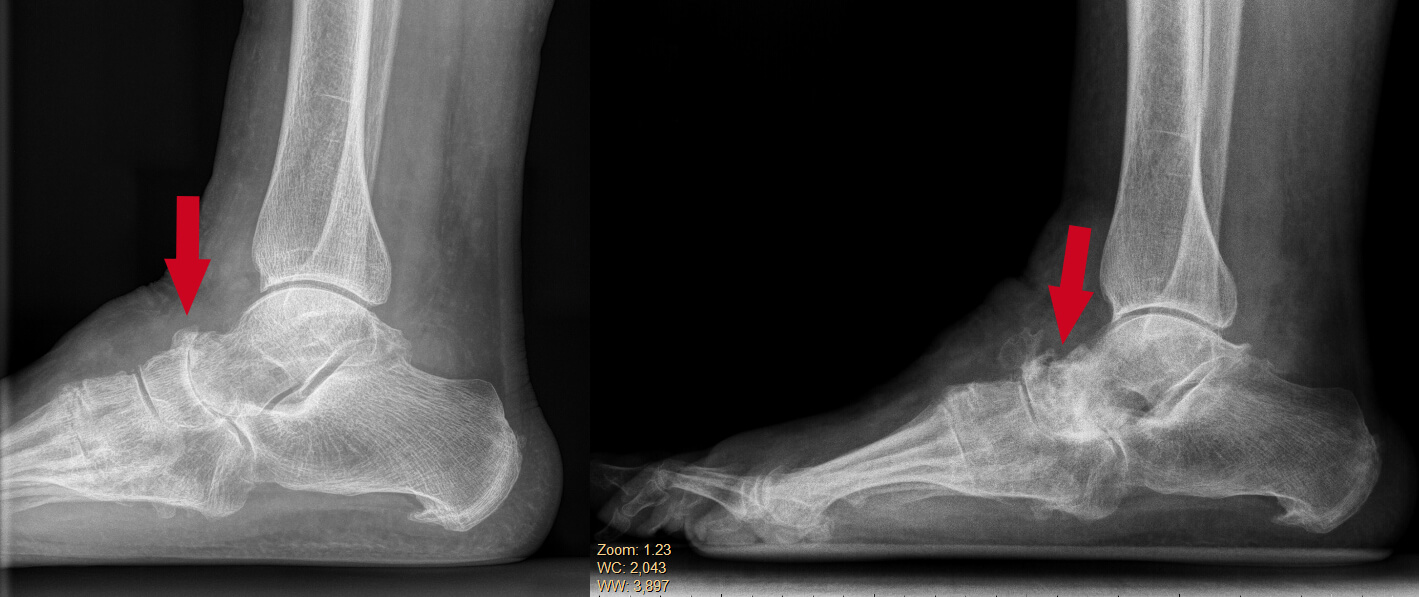

Die is een zijdelingse röntgen opname van een voet met de ziekte van Müller-Weiss. De rechter foto is dezelfde voet drie jaar later. Er is een forse progressie van de ziekte van Müller-Weiss te zien.